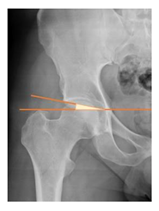

| Acetabular index | The angle described between the line running through the medial edge of the sclerotic acetabular zone and through the lateral sourcil, and its horizontal line | 3–13° | ![]() |